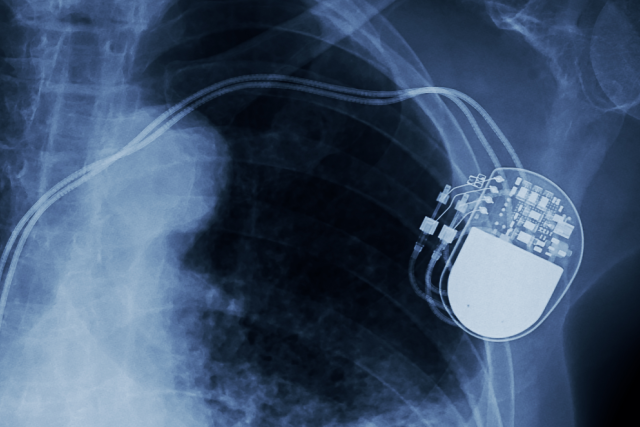

An X-ray shows a pacemaker implanted in the upper left chest of a human, with wires extending down into the heart region.

Dear Reader: A pacemaker is a small medical device that keeps the heart beating at a steady rhythm. It consists of sensors, which monitor the heart rate, and a battery-operated pulse generator, which sends corrective impulses to the heart. A pacemaker can adjust a heartbeat that is too slow, and it can correct potentially dangerous heart arrhythmias. A catheter is used to thread the sensors through a vein that leads to the heart. The pulse generator, which is about the size of a matchbox (or smaller), is implanted just beneath the skin of the chest. (A new, tiny pacemaker known as a Micra, which consists of a single piece, is placed directly into the heart.)